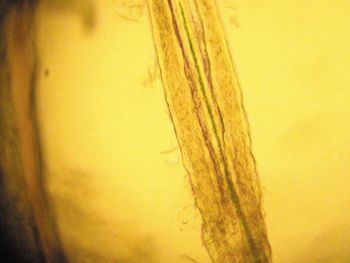

Join veterinary radiologist Dr. Kathy Spaulding on an ultrasonic tour of the intestinal tract and see which findings might indicate disease.

When it comes to chronic gastrointestinal cases, its time to throw out your outdated terms and diagnoses.